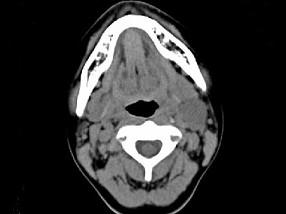

问题 女,16岁,发现左颈部肿块两年,CT如图所示,最可能的诊断为 ( )

选项 A、左侧鳃裂囊肿 B、囊性转移癌 C、咽部神经鞘瘤 D、咽旁脓肿 E、囊状水瘤

答案 A